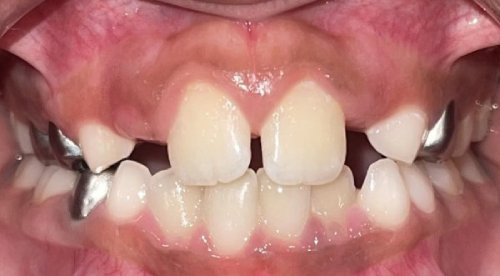

Actual Patient: Alexander

Alexander Before 4 Alexander After 4

Severe “Underbite”, Narrow Jaws, Adult Teeth Not Growing In

Alexander Before 1 Alexander After 1

Front View

Top View

Right & Left Sides